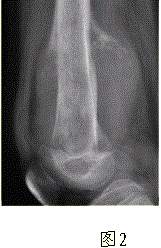

问题 患者男,16岁,左大腿下部疼痛伴肿胀2个月,逐渐加重。自感左膝上方胀痛,尤以夜间为著,伴行走困难。既往史及家族史无特殊。查体:左大腿下部明显肿胀,皮温较对侧升高。碱性磷酸酶明显增高。股骨平片及MRI见下图。 应该首先考虑的诊断为

选项 A.急性化脓性骨髓炎 B.骨结核 C.骨肉瘤 D.畸形性骨炎 E.骨转移瘤 F.软骨肉瘤

答案 C